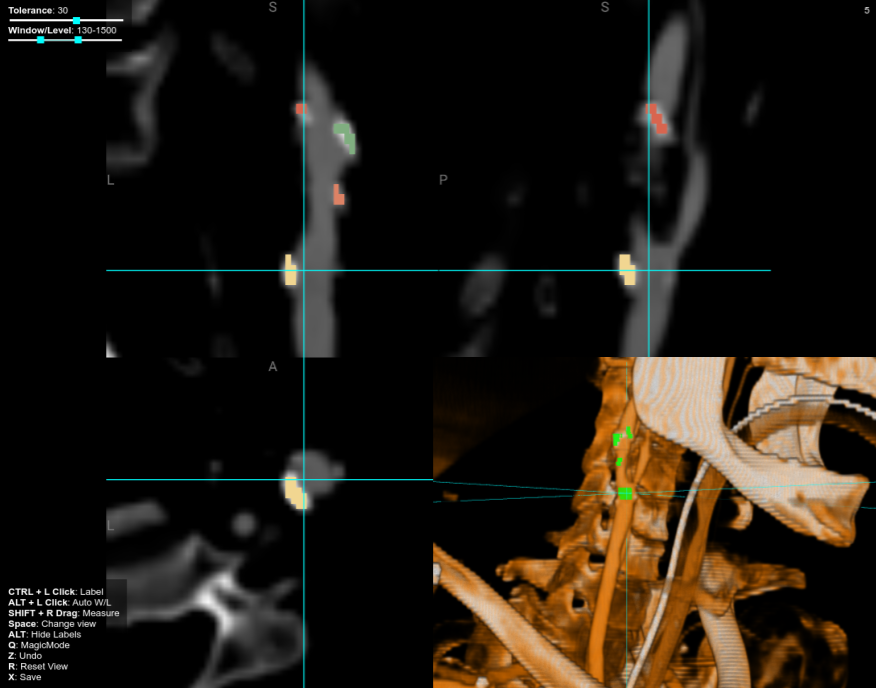

2D Image Modalities

What about CT, MRI, EM?

Image Volumes

2D

3D

Slice-based Volume Rendering

Volume Rendering with Ray Casting